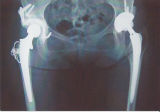

私は両股関節が人工関節なのですが、右側は28年前、左側は11年前に

手術しました。この28年前の人工関節が一部摩耗により壊れ、

入れ替えの手術でした。